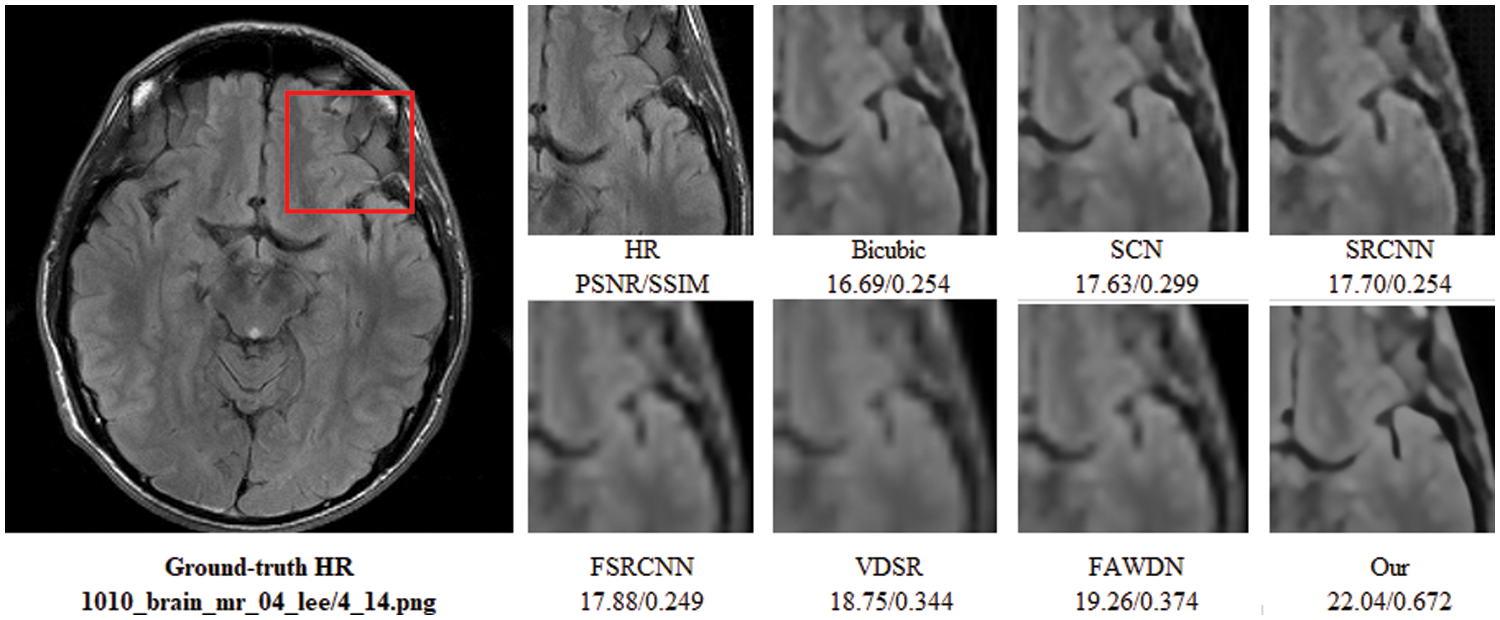

To evaluate the comparison quality of image SR methods with the proposed approach, particularly Bicubic, A+, SelfExSR, RFL, SRCNN, FSRCNN, VDSR, DRCN, LapSRN, DRRN, and IDN techniques. Table 2 presents the quantitative results of different algorithms on the Set5, Set14, BSDS100, and Urban100 test data sets, with an enlargement factor of 2×, 3×, and 4× accordingly. Fig. 6 shows the quantitative performance of state-of-the-art approaches in terms of PSNR vs. network parameters. Our proposed model (IRMRIS) has fewer parameters than the VDSR, DRCN, and LapSRN. Despite having a lower footprint as compared to CNN-based approaches, the performance of the proposed model was demonstrated to be state-of-the-art. As compared to the Bicubic, A+, SelfExSR, RFL, SRCNN, FSRCNN, VDSR, DRCN, and LapSRN. Furthermore, our IRMRIS model has about 1.87, 0.78, 0.79, 0.86, 0.67, 0.56, 0.56, 0.29, and 0.27 dB improvement on the BSDS100 dataset for enlargement factor 3× image SR. Figs. 7–10 present a visual performance comparison of the brain MRI images at enlargement factor 4× SR. The result of the baseline method (bicubic) and SRCNN clearly shows blurry MRI image, but our proposed IRMRIS reconstruct the best results as compared to another state-of-the-art methods MRI image SR.

Figure 10: Perceptual quality comparison of our method with other deep learning-based methods using MRI images at 4× super-resolution. The image is obtained from “1010_brain_mr_04_lee/4_14.png” dataset